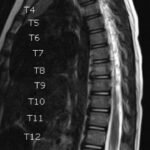

Pediatric neuroblastoma is famously characterized by an abdominal mass in a toddler with “raccoon eyes,” Horner syndrome, and/or opsoclonus myoclonus. However, rare cases may present with non-discrete symptoms and signs which create challenges for timely diagnosis. This case depicts a toddler with bulbar symptoms, including bilateral ptosis, dysphagia, drooling, head tilt and ataxia in a post-viral course mimicking other neurologic diagnoses, including myasthenia gravis. Magnetic resonance imaging (MRI) of the brain and spine uncovered a right adrenal mass along with heterogenous enhancement in multiple vertebral bodies and the clivus, consistent with metastatic disease. A diagnosis of neuroblastoma was confirmed with elevated homovanillic acid (HMA) and vanillylmandelic acid (VMA) levels and adrenal biopsy. The patient was treated with plasmapheresis for suspected paraneoplastic neurological syndrome and subsequent chemotherapy. In this case presentation, we review neurologic syndromes causing acute-onset pediatric bulbar weakness along with the patient’s key MRI findings.